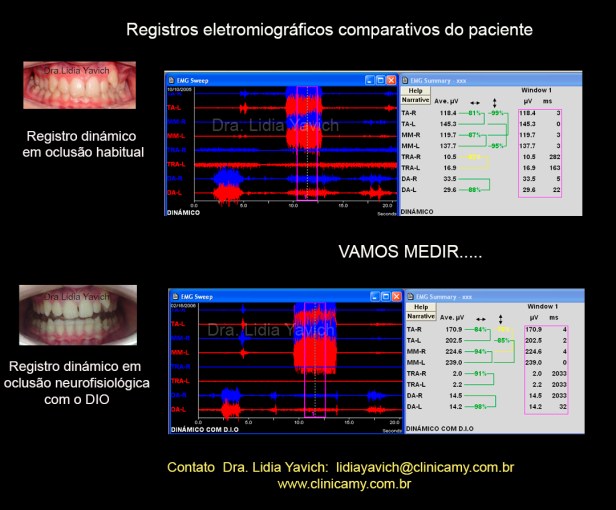

Eletromiografia de superfície dinâmica do paciente em oclusão habitual antes do tratamento.

São medidos:

Temporais anteriores direito e esquerdo.

Masseteres direito e esquerdo

Digástricos direito e esquerdo

Trapézio superior direito e esquerdo

Ativação dos digástricos no fechamento, sendo que estes músculos só devem ser ativados na abertura.

Importante ativação dos trapézios superiores mesmo o paciente sendo instruído a abaixar os ombros ele ativa ambos os trapézios durante todo o exame.

No tratamento, 0 dispositivo instalado é controlado por meio de eletromiografia de superfície para avaliar e comparar a sua função em relação aos registros anteriores.

Comparação dos registros eletromiográficos antes, durante e após o tratamento.